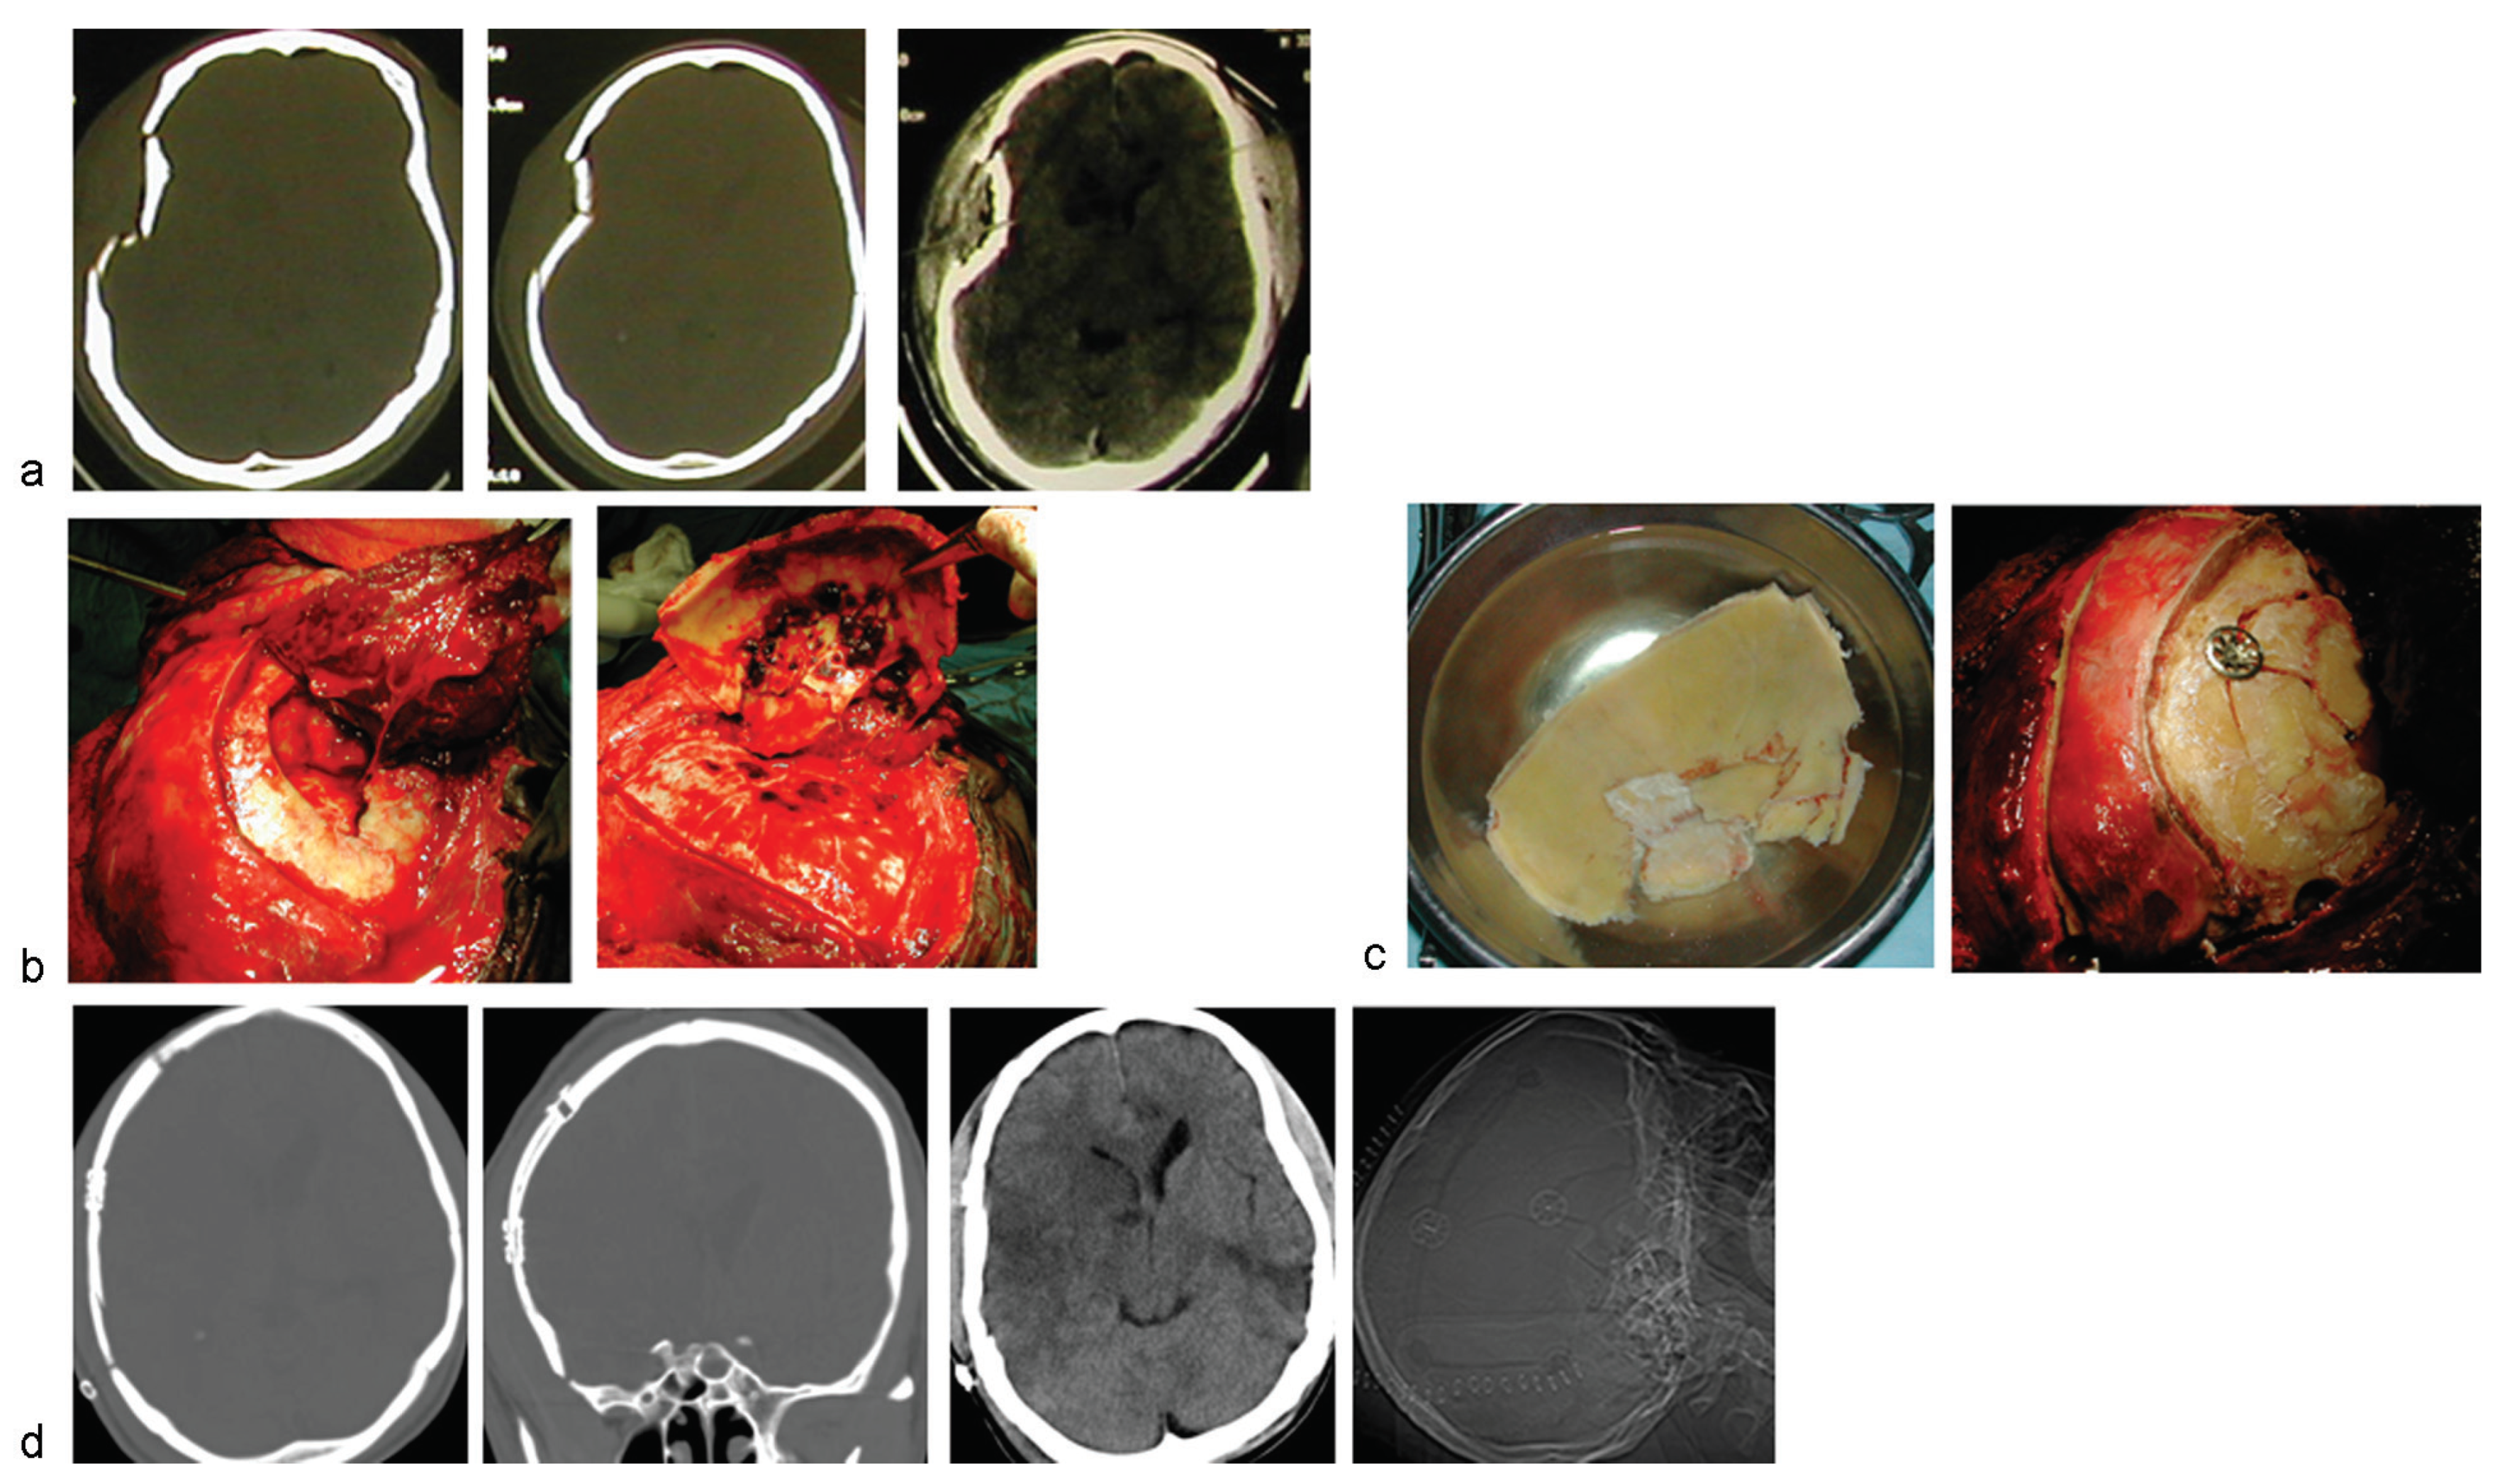

Figure 3) are raised to expose the cranial-facial fracture lines. For elevation of the fracture fragments, attempts are made to achieve osteotomies and calvarial craniotomies that include intact bone segments to facilitate the reassembly of the fracture fragments (

Only one case was a closed fracture, and the rest were compound craniofacial skeletal disruption, with significant, ragged lacerations in three cases (

Figure 3). Most (16/18, 88.8%) of the patients presented with mild HI, Glasgow coma scale of 13 to 15; one case each with moderate and severe HI, respectively, and 14 (85.7%) had history of loss of consciousness that ranged in duration from 10 minutes to 5 days (median, 48 hours). This is in keeping with their delayed presentation to us: some of them were referred from the peripheral health facilities to our neurosurgical service for the operative treatment of their skull/brain injury after regaining some level of consciousness. Associated intracranial injuries included pneumocephalus in six (five of them significant); acute extradural hematoma in four and subdural in two, and brain contusions in nine (

Figure 3). Extracranial-associated injuries were pelvic fracture in two; femoral fracture in two, one open and the other one closed; and maxillofacial skeletal injuries in six: four simple nonsurgical fractures and two more complex ones.

Figure 2 and

Figure 3).